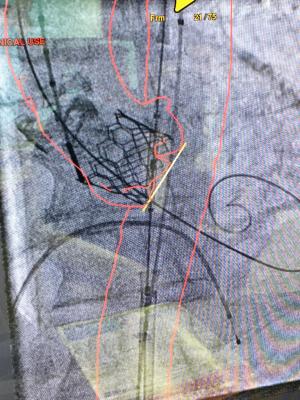

All major vendors offering advanced visualization software now offer structural heart planning. This is an example of GE Healthcare's Valve Assist software being used to determine the best location of a transseptal puncture to deliver a left atrial appendage (LAA) occluder.